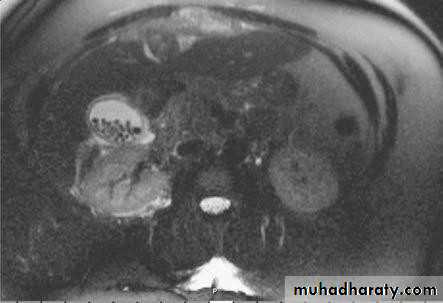

• CT SCAN

• Computed tomography scan demonstrating a gallstone

• within the gall bladder (arrowed).

• MRCP

• Magnetic resonance cholangio- pancreatography crosssectional

• image demonstrating a hilar mass (thick

• arrow) and gallstones (thin arrow)